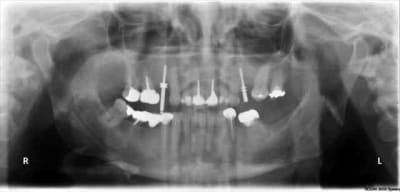

tiens...un ptit cas...

dans ce petit cas...j'ai commencé avec le kit MIS...et fini ma voie crestale avec le kit HBS...

ok, c'est un mini soulevé...mais bon , c'est un exemple...

juste une précision...premier foret 1.3mm sur 8mm...expansion pour mettre un implant de 4x10...

j'ai juste "léché" la préparation du site final avec le foret terminal du système...sur 8mm...avant d'insérer l'implant...stab primaire au top...blocage à 40 Ncm...

rien...une cloison du sinus...;-))

???? tu as un pano ou un scan je ne situe pas ça comme une cloison, mais je vois mal.

j'ai la pano au cab...pas de problème...çà peut aussi être un épaississement de la membrane dans ce cloisonnement...il a eu un bon rhume quelques semaines avant...